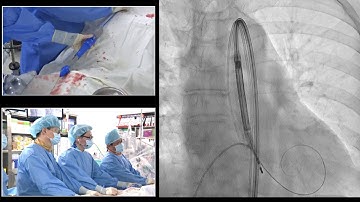

[AP VALVES & SH 2024] Opening, Live Case & Lecture 1: TAVR